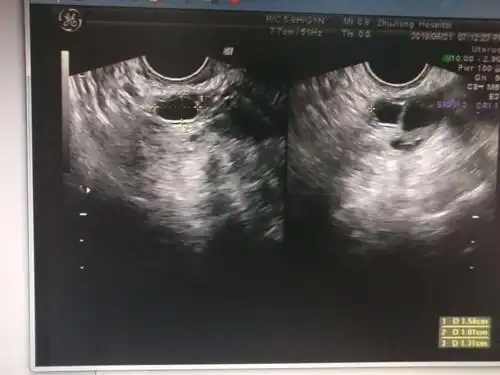

月经第17天卵泡监测2221

卵泡监测,帮忙看下吧,继续测试吧

卵泡监测